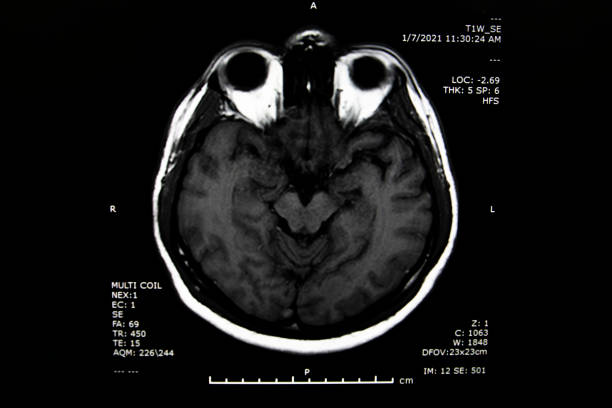

뇌경색 후유증은 심각한 장애를 남길 수 있는 신체적, 정신적 문제를 야기할 수 있는 중요한 주제입니다.

뇌경색 의심이 된다면 빠르게 대응해서 치료를 하는게 좋습니다.

뇌경색 후유증은 다양한 증상을 유발할 수 있습니다. 이러한 증상은 흔히 다음과 같이 나눌 수 있습니다.